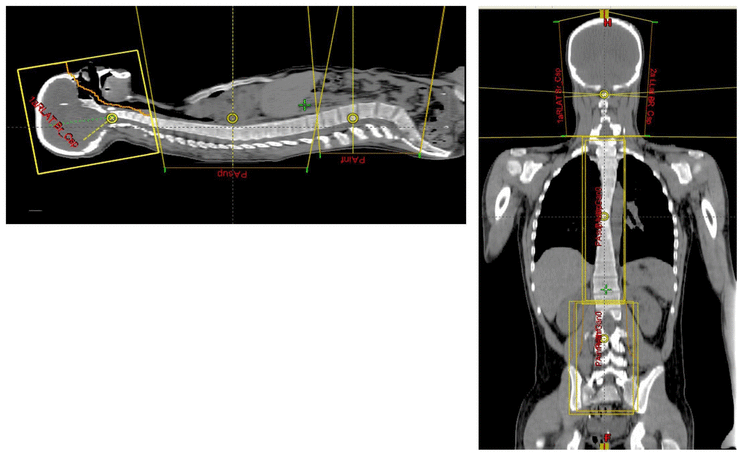

Cranio-spinal irradiation is technically challenging. There are a minimum of 3 and usually 4 beam divergence matches that must be accomplished. The brain is usually irradiated with opposed lateral fields, while the spine is irradiated with an orthogonal posterior-anterior field. The PA fields cover the spine portion. Key junctions are the upper PA field to the lateral fields, and the two PA fields. Traditionally the treatment fields have been set up with fluoroscopic simulators, which is time consuming and difficult. Several calculations are required. The following summarizes this type of technique. The patient is simulated prone with the neck extended. The match point of the upper PA and lateral fields is selected. This is usually selected in the cervical spine to minimize dose to larynx and thyroid. This also gave additional room to "feather the borders" to minimize the possibility of overdose/underdose due to setup uncertainty and variance. The setup junctions were feathered every 9 Gy (1/week) to insure uniformity of dose to the match lines. More modern techniques allow supine positioning with an aquaplast head mask, with or without trunk immobilization but with skin marks to determine straightness of setup match using room lasers. The basic principles are shown:

Adult medulloblastomas appear to have about the same prognosis as pediatric medulloblastomas. It is not clear if the biology is different. Post operative radiation therapy should commence within 28-30 days post resection whenever possible. Radiation therapy is initially delivered to the craniospinal axis followed by the involved site boost fields. The CSI is treated using opposed laterals to the posterior fossa with collimator rotated to match the superior PA field used for the spinal portion of the treatment. Great care must be used to match the field junctions. There are two competing divergences from each field. The lateral fields have divergence inferiorly into the superior PA spinal field, and the spinal field diverges superiorl into the lateral field. BOTH OF THESE DIVERGENCES MUST BE ACCOUNTED FOR AND CORRECTED. Once the PA field length in known, the collimator rotation of the lateral fields can be calculated (θ = atn(Len/2*SAD) )